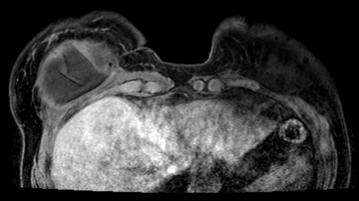

Standardized body region labelling of individual images provides data that can improve human and computer use of medical images. A CNN-based classifier was developed to identify body regions in CT and MRI. 17 CT (18 MRI) body regions covering the entire human body were defined for the classification task. Three retrospective databases were built for the AI model training, validation, and testing, with a balanced distribution of studies per body region. The test databases originated from a different healthcare network. Accuracy, recall and precision of the classifier was evaluated for patient age, patient gender, institution, scanner manufacturer, contrast, slice thickness, MRI sequence, and CT kernel. The data included a retrospective cohort of 2,934 anonymized CT cases (training: 1,804 studies, validation: 602 studies, test: 528 studies) and 3,185 anonymized MRI cases (training: 1,911 studies, validation: 636 studies, test: 638 studies). 27 institutions from primary care hospitals, community hospitals and imaging centers contributed to the test datasets. The data included cases of all genders in equal proportions and subjects aged from a few months old to +90 years old. An image-level prediction accuracy of 91.9% (90.2 - 92.1) for CT, and 94.2% (92.0 - 95.6) for MRI was achieved. The classification results were robust across all body regions and confounding factors. Due to limited data, performance results for subjects under 10 years-old could not be reliably evaluated. We show that deep learning models can classify CT and MRI images by body region including lower and upper extremities with high accuracy.